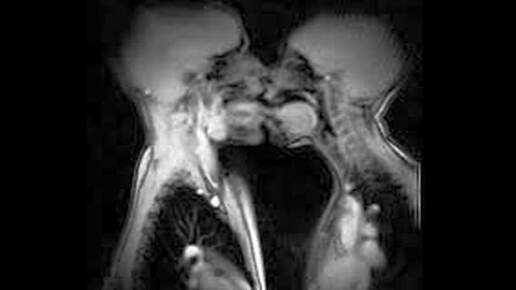

Научные данные о половом акте: что измерили, сколько длилось и какие открытия ошеломили исследователей

Секс — одна из самых интимных сфер жизни, но при этом — одна из самых изучаемых с научной точки зрения. За последние 70 лет учёные провели сотни исследований, чтобы понять, как люди занимаются сексом, сколько это длится, что влияет на удовлетворённость и какие параметры можно измерить объективно. Ниже — сводка самых достоверных, проверенных и иногда удивительных данных. Самый частый вопрос — и самый исследованный. Категория; Продолжительность (медиана) Весь мир; 5,4 минуты США / Канада; 6,2 минуты...